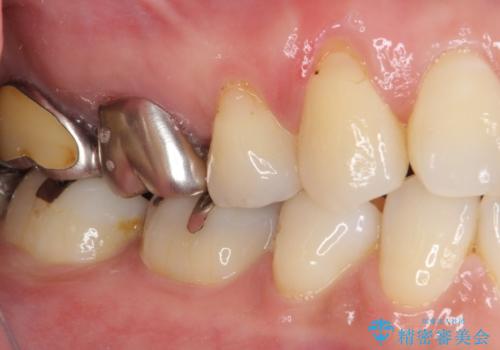

- 口を開けたときに目立ってしまう銀歯をセラミックに替えたいとのことで来院された患者様です。

上顎や親知らずにも銀歯がありましたが、今回の治療では目立つ下顎の銀歯4歯をセラミッククラウンやセラミックインレーに置き換えることにしました。

話をする度に相手の視線が銀歯に注がれている気がしているとのことでしたが、目立つ銀歯を自然な色合いに仕上げることができ、患者様には大変満足していただきました。